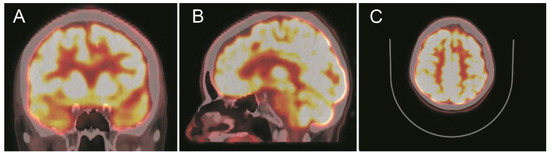

2. Case Presentation